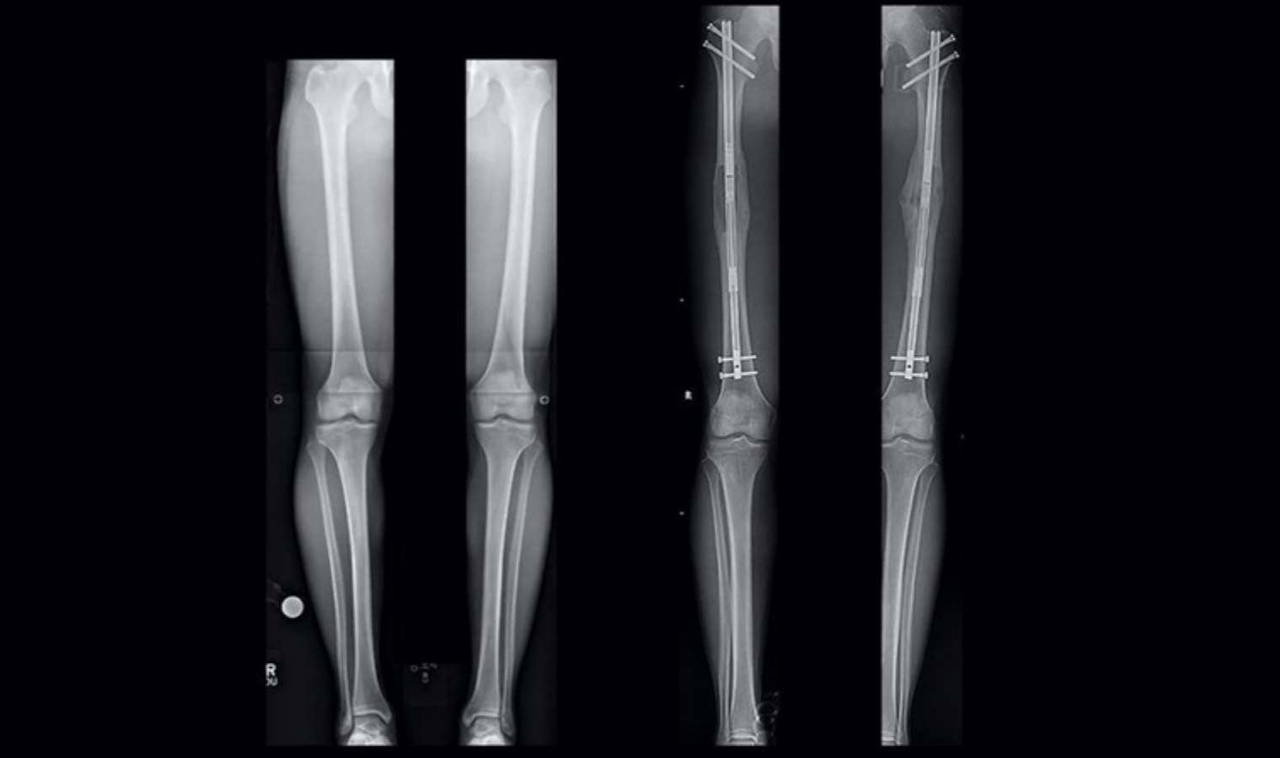

"Kemiğe, manyetik bir uzatma çubuğu ve pimler yerleştirilir. Bu sayede bacağın, belirli bir süre boyunca kontrollü olarak uzaması sağlanır..."

"Rekonstrüktif cerrah, operasyona tabi olan bacaktaki küçük kesilerden, uyluk veya kaval kemiği üzerinde cerrahi bir osteomi (kırık) gerçekleştirir."

Evet, doğru okudunuz; operasyon kapsamında doktorunuzun belirli noktalardan 'bacaklarınızı kırması' gerekiyor.